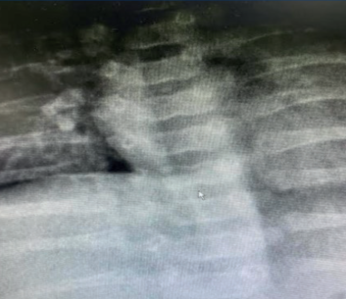

Se indicaron estudios para evaluar afectación multisistémica: radiografía de columna vertebral: cuerpos vertebrales dorsales D7 y D11 con morfología sugestiva de vértebras “en mariposa” (Figura 2). Ecocardiograma: estenosis leve de rama pulmonar derecha. Valoración oftalmológica: embriotoxon posterior en ambos ojos, fondo de ojo sin alteraciones. Biopsia hepática: colestasis neonatal de patrón mixto, ductopenia, índice ducto/espacio porta 2/28 y hepatitis neonatal.

Los hallazgos en el sistema esquelético más reportados son las vértebras torácicas en forma de alas de mariposa. Se deben a fusiones anormales de la columna vertebral que conducen a hendiduras sagitales en 80% de los casos, tal como se evidencia en esta paciente.